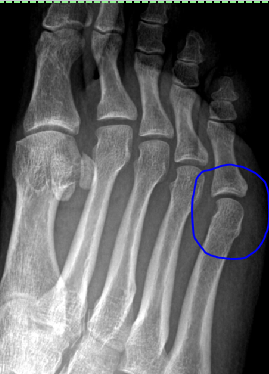

Stress fracture, bone abnormalityor just all in my head? Saw the foot doctor today to get the X-rays read, and like Google had already told me — if there’s a stress fracture, it’s not readily …

So.Um, yea. It’s been awhile, hasn’t it?No good excuses, though I’ve been struggling (and losing) to keep forward momentum going. About 2 weeks ago, I finally made an appointment with a doctor to see about …